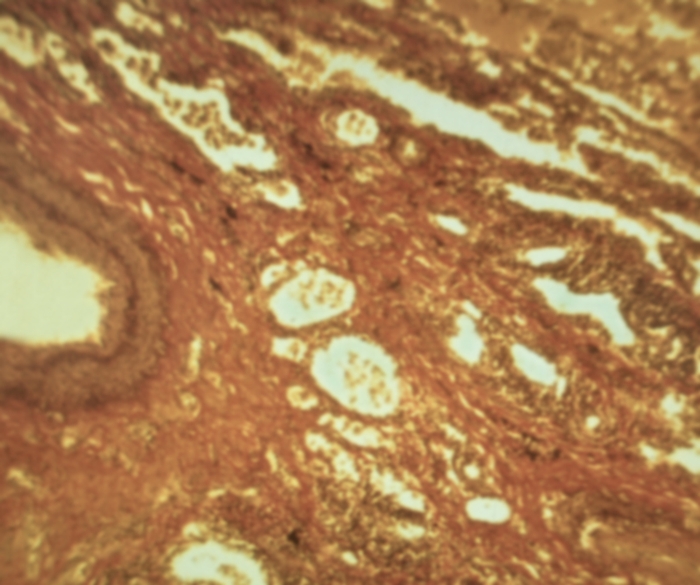

Карнификация Легкого: Микропрепараты и Диагностика

Раздел: Калейдоскоп образов